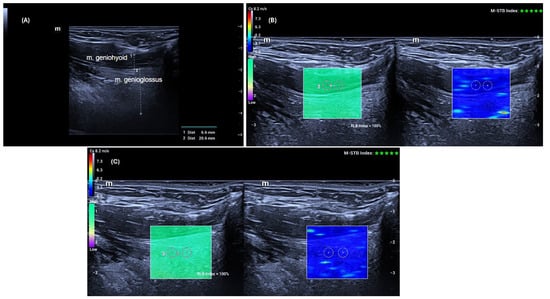

All data were obtained using the SWE mode of the same US device (Mindray Resona I9, Shenzhen, China). Measurements were performed with a high-frequency linear transducer (L14-3 Ws) by a radiologist with 14 years of experience. Advanced technologies provided by the manufacturer supported the accuracy and stability of the measurements. The “Motion Stability” (M-STB) function allowed real-time monitoring of motion in the target area, and measurements were only recorded when a 4–5-star rating and green indicator were present. Additionally, image quality was assessed using the “Reliability Map” (RLB MAP) function, and measurements were taken only in areas with a reliability index of ≥90%. In cases of low signal quality or no signal, the measurement was considered invalid and repeated. Additionally, to increase measurement reliability, the interquartile range (IQR) and IQR/median ratios automatically calculated by the device were taken into account, and an IQR/median ratio of <0.30 was accepted as the standard [13]. Figure 1 shows an example of grayscale US and SWE measurements of the GG and GH muscles.

Figure 1. Geniohyoid and Genioglossus muscle thickness (A) was measured by the hypoechoic muscle tissue located between the superficial (anterior) and deep (posterior) fasciae of the muscle. Geniohyoid muscle elasticity (B) and Genioglossus muscle elasticity (C) measurements were taken in the regions of interest (ROI), with the ROI dimensions adjusted to 3 × 3 mm, and five measurements were obtained from each muscle. The ‘Motion Stability’ (M-STB) function was only measured at a 4–5-star level and in the presence of a green indicator. The ‘Reliability Map’ (RLB MAP) measurements were taken from areas with an RLB index of 90% or above.